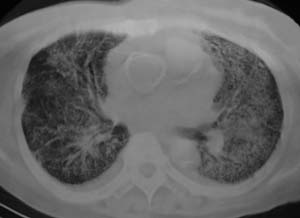

以下是引用liaizhi在2007-7-6 0:05:00的发言:[br]双肺纹理膜糊,沿纹理走行有班点状高密度影。考虑心衰并肺水肿。

以下是引用andymaomao在2007-7-5 22:23:00的发言:[br]双上肺明显,考虑心衰并肺水肿,双侧胸腔少量积液!另不除外肺泡蛋白沉着症及肺泡ca可能。[br]联想机制——心脏病(代偿期)--肺部淤血--后可能并感染致病情加重--抗炎治疗好转,但肺淤血严重,心功能失代偿--心衰而死亡!

以下是引用拾荒者在2007-7-6 13:06:00的发言:[br]支持:心衰,肺水肿及ards